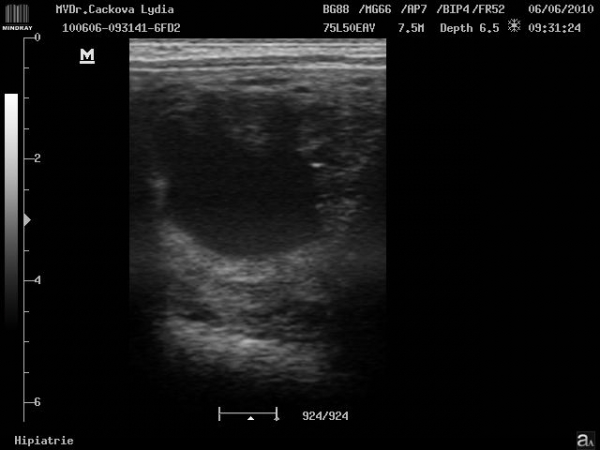

embryo kolem 21.dne